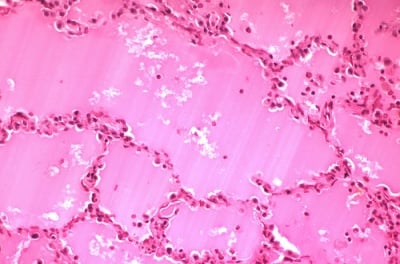

Какво представлява отока от патологична гледна точка. Видове отоци....

Тук се включват хиперемията, емболията, тромбозата, кръвоизливите и др....